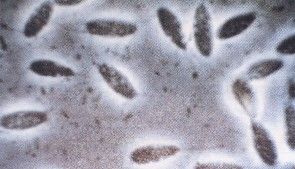

鴿子血液原蟲病是由孢子綱、瘧原蟲科中鴿血變原蟲入侵鴿紅細胞內而引發的一種血液原蟲病。

鴿血變原蟲禽血變原蟲常見種有火雞血變原蟲,鴿血變原蟲,水禽血變原蟲,而鴿血變原蟲最為常見。禽血變原蟲殖生殖發生在內臟器官的內皮細胞里,配子體出現在循環的紅細胞內,孢子生殖發生在昆蟲體內。